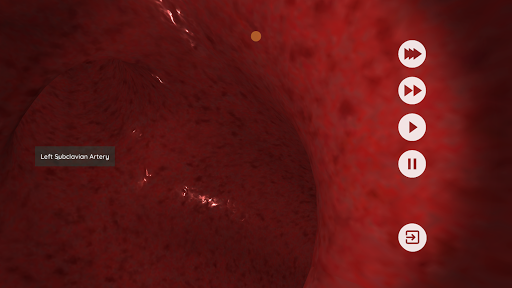

Anatomyou VR to edukacyjna aplikacja mobilna, która prezentuje w sposób wciągający ludzką anatomię.

Korzystając z wirtualnej rzeczywistości, będziesz w stanie poruszać się wzdłuż struktur anatomicznych, stając się częścią ludzkiej anatomii: układu rozrodczego układu krążenia, oddechowego, trawiennego, moczowego, łzowego i żeńskiego.

Anatomyou VR może być używany w dwóch różnych trybach: Virtual Reality i Fullscreen.

W trybie wirtualnej rzeczywistości urządzenie mobilne (smartfon) musi być umieszczone w gadżecie wirtualnej rzeczywistości, aby cieszyć się w pełni wciągającym doświadczeniem. Użytkownik może wchodzić w interakcję z elementami sterującymi nawigacją i elementami informacji anatomicznej, kierując je na cel.